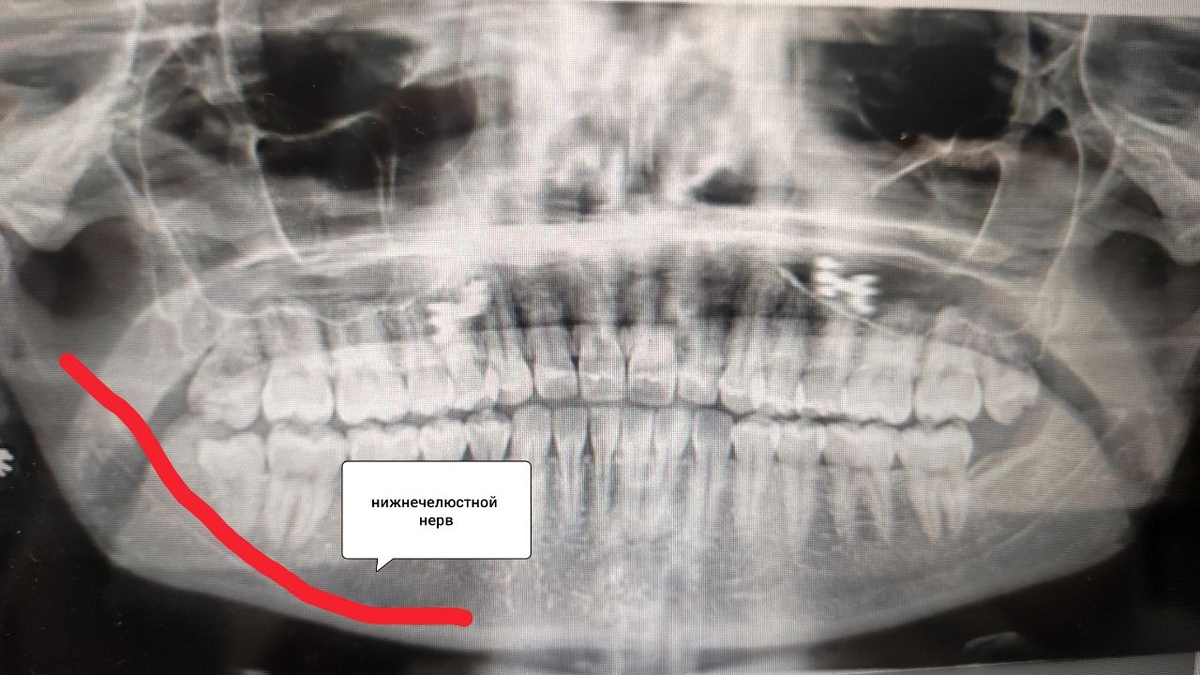

Повреждение нерва. При удалении зуба мудрости, особенно если его корни близко расположены к нижнечелюстному нерву, возможно его случайное травмирование. Это приводит к парестезии (онемению) языка, губы или подбородка.

Сдавление нерва отёком. После операции отёк тканей может временно сдавливать нервные волокна. Обычно это проходит в течение 2 недель.

Дополнительные обследования (рентген, КТ) для исключения осложнений.